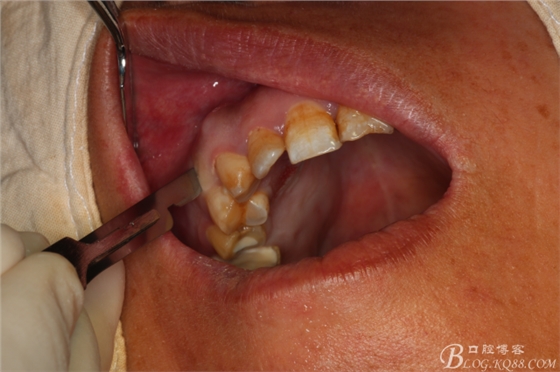

圖1.術(shù)前患者的口內(nèi)照片:15、16頰側(cè)黏膜膨隆、捫診有乒乓感